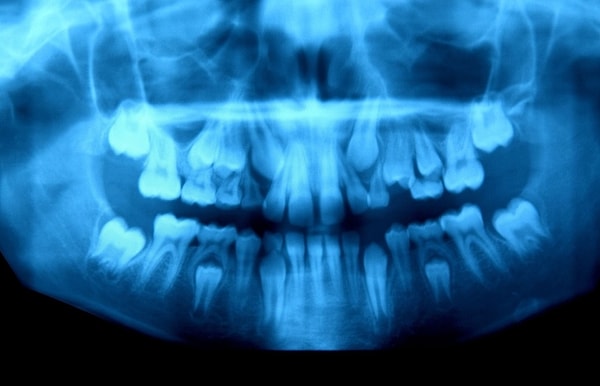

2. Süt dişleriyle kalıcı dişleri yer değiştiren 10 yaşındaki bir erkek çocuğunun çenesi: